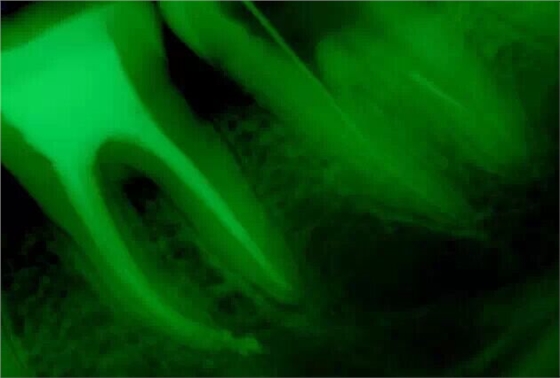

沒辦法只能掏針了,先形成側(cè)方通路,然后用超聲慢慢往出震。

震出一半時照的X片